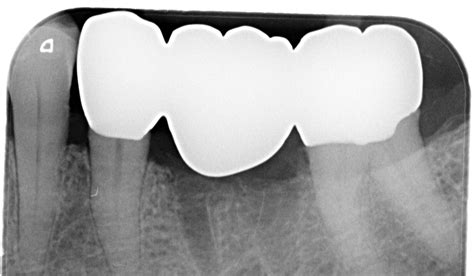

A 3 unit bridge dental appliance is a custom-made restoration designed to replace a single missing tooth. The "unit" count refers to the total number of crowns involved in the structure:

• Two Abutment Crowns: These are the crowns that fit over the healthy, natural teeth on either side of the gap. These teeth serve as the anchors or supports for the bridge.

• One Pontic: This is the prosthetic tooth that sits in the middle, effectively filling the space left by the missing natural tooth.

By creating this cohesive unit, your dentist can restore both the functionality and the aesthetic appearance of your dental arch. Unlike removable dentures, which can feel bulky or move around, a bridge is permanently cemented in place, providing a stable and comfortable experience similar to your natural teeth.